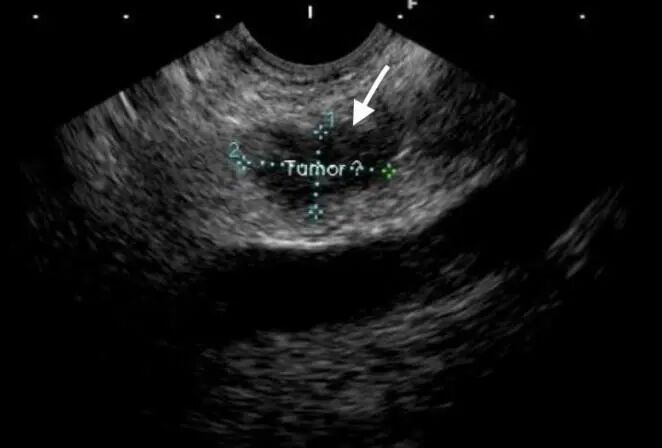

超声内镜下可以清晰地显示患者胰腺肿瘤

(白色箭头指向处)

凭借娴熟的超声内镜操作技术,以及先进设备的清晰成像,毛益申医生快速明确患者胰腺颈部确实存在一处15×9mm的肿瘤,同时确认了肝脏多发病灶符合肿瘤性病变的表现。随后,他分别对肝脏及胰腺的病灶进行穿刺活检术,获取了充足的组织条送病理检查。整个流程仅耗时约30分钟,术后患者麻醉苏醒后除轻度咽痛外无任何不适。